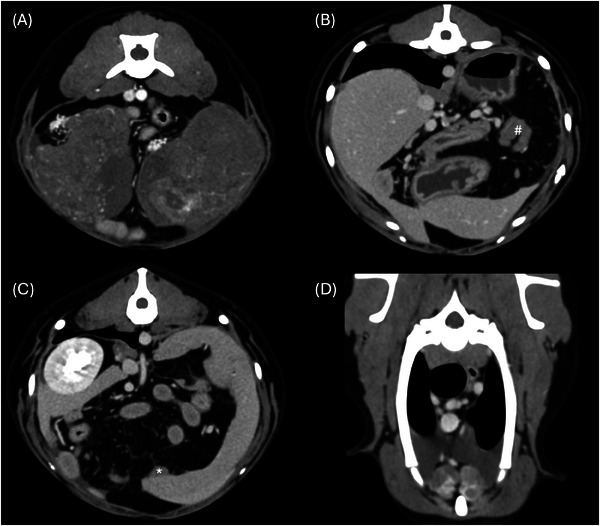

The aim of this retrospective multicentric case series is to describe the CT findings of ovarian neoplasia in dogs. Twenty dogs with pre- and postcontrast CT exams and cytological/histological diagnosis of ovarian neoplasia were included. Five dogs presented with bilateral tumors, for a total of 25 neoplasms: 15 carcinomas (4 bilateral), 4 granulosa cell tumors, 2 poorly differentiated malignant neoplasia (bilateral), 2 luteomas, 1 teratoma, 1 dysgerminoma. In two dogs, the tumor developed from an ovarian remnant. Ovarian tumors showed variable size, lobulated shape, and precontrast heterogenous appearance. Mineral foci and/or fat components were rare, observed in teratoma, granulosa cell tumors (2), and ovarian carcinoma. Tumor type was not found to be associated with any CT features. Larger masses were more likely located in the central abdomen ventral to the ipsilateral kidney, demonstrated signs of tumor rupture, and were associated with abdominal or sternal lymphadenopathy and peritoneal effusion. A tortuous ovarian artery was constantly detectable, associated with an enlarged gonadal vein (12 cases). Related cavitary changes were peritoneal effusion (14 dogs) and sternal lymphadenopathy (7 dogs). Presumed or confirmed metastasis was reported in 9 of 20 cases, with CT evidence of transcoelomic (serosal thickening, peritoneal nodules, omental cake, implant lesions to the liver, spleen, and diaphragm), lymphatic and hematogenous spread (lungs, liver, bone, muscles, and spleen). In conclusion, the present study reports the CT features of different canine ovarian neoplasia. A tortuous ovarian artery may be useful to consistently recognize the ovarian origin of a large abdominal mass.